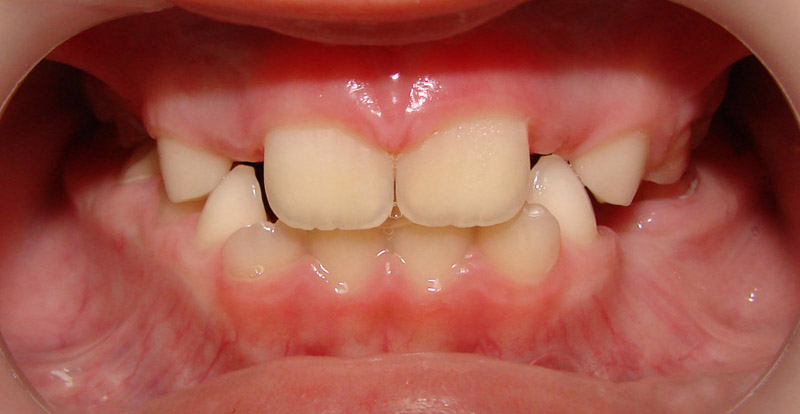

Начну с самого простого. Мальчик, 6 лет. Носил съемную плстинку 4 мес. В таком возрасте брекеты еще, как правило, не используют.